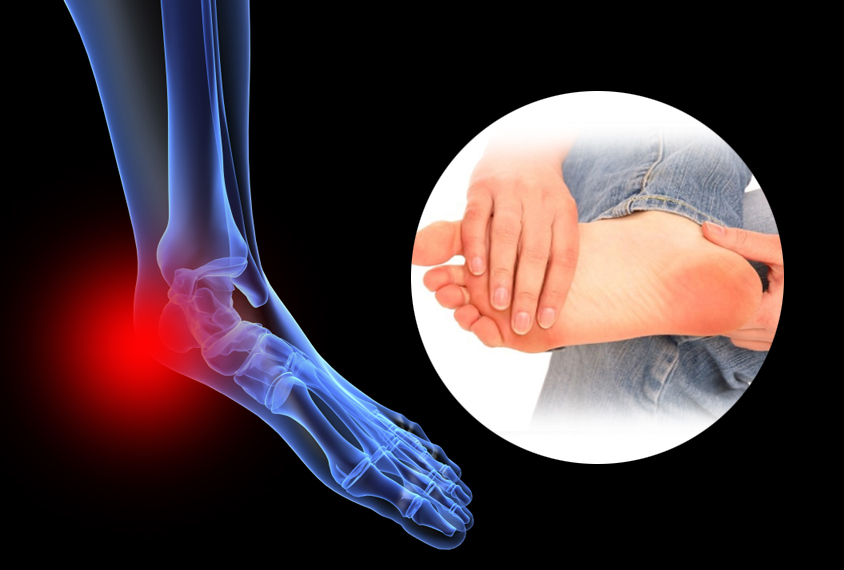

안녕하세요! 오늘은 많은 분들이 경험하는 발바닥 통증의 원인에 대해 알아보려고 합니다. 발바닥은 우리 몸을 지탱하고 이동하는 데 중요한 역할을 하는 부위이기 때문에, 통증이 발생하면 일상생활에 큰 지장을 줄 수 있습니다. 발바닥 통증의 다양한 원인을 살펴보고, 이를 예방하고 관리하는 방법에 대해 알아보도록 하겠습니다.

발바닥통증의 원인 발바닥통증의 원인